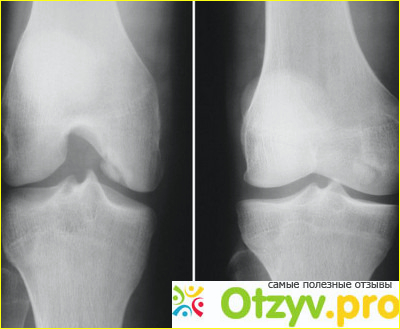

Спустя где-то пять-шесть месяцев колени начали болеть регулярно от постоянного сидения за столом. Ввиду особенностей работы от этого никуда не деться. В этот раз я не стала дожидаться ужасных приступов боли, а начала действовать. Знакомая фармацевт посоветовала взять препарат ферматрон - обезбаливающее при болях в суставах. Это оказались ампулки с жидкостью. Уколы делали мне во все той же больнице прям в коленку, один раз в неделю. Тем, у кого запущенная ситуация, нужно делать до трех инъекций, но мне хватало так. Уколы болезненные, но как иначе, в коленный сустав больно. Раствор 100 мл стоит примерно 160 гривен.